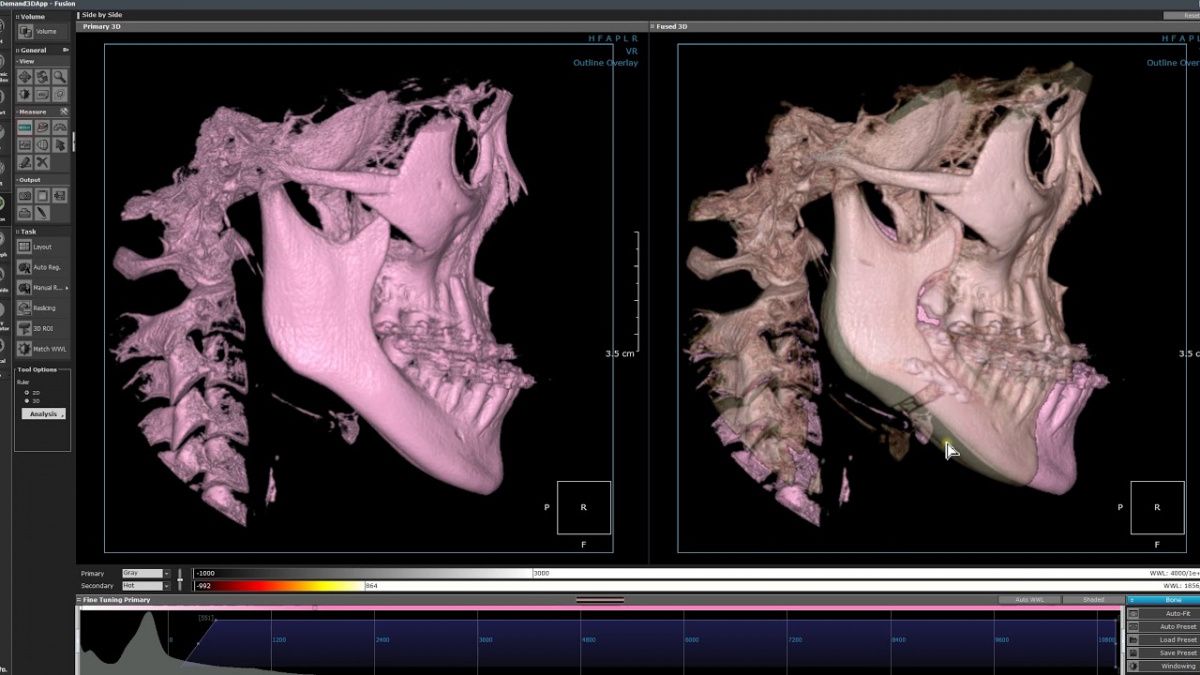

Немаловажным, а может главным вопросом, является универсальность программы-просмотровщика, в которой будут работать врачи-стоматологи. У Papaya 3D есть два варианта программ: Triana и OnDemand3D. Оба просмотровщика обладают схожим интерфейсом и имеют самые важные опции, а именно:

Таким образом обе программы являются простыми в пользовании, но обладающими обширным спектром возможностей для диагностики любыми специалистами-стоматологами. В данные программы происходит загрузка классических файлов DICOM 3.0, которые являются общепринятым форматом записи данных пациента. Это важный момент, так как позволяют врачу, имеющему полную версию программы загружать даже сторонние исследования и просматривать их в этих программах. Простота в освоении этих программ позволяет даже специалисту, не работающему раннее с этими программами, быстро адаптироваться и получить качественную информацию. Возможность выгрузки STL-файла дополнительно создает возможность интегрировать данные с цифровым ортопедическим протоколом.